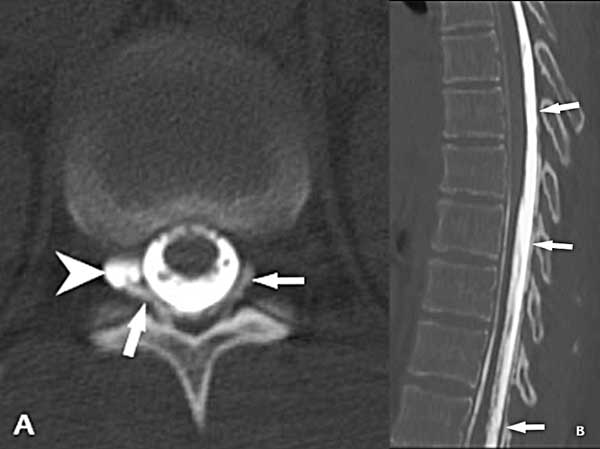

En julio del 2023 se efectuó una inyección de contraste yodado (iopamidol 370) por vía intratecal lumbar a razón de 1 cm3/segundo en la camilla del tomógrafo (GE light speed de 16 hileras) en decúbito ventral. Esto ocasionó una importante cefalea que fue cediendo en los minutos siguientes. Inmediatamente concluida la inyección, se realizó la adquisición en modo helicoidal de la columna lumbar y posteriormente se fueron obteniendo secuencias de la columna dorsal siguiendo el ascenso del contraste. A nivel T11/12 se identificó un quiste de la vaina radicular derecha que mostraba extravasación del medio de contraste al espacio extradural en dirección cefálica hasta aproximadamente T7 (Figura 3).

Figura 3. Mielo-TC. A) Corte axial a nivel T12/L1 que muestra el llenado del quiste radicular derecho (punta de flecha) y la salida del medio de contraste al espacio extradural (flechas). B) Reconstrucción sagital de la columna dorsal que muestra el ascenso del medio de contraste por fuera de la duramadre dorsal hasta el nivel T7 (flechas).